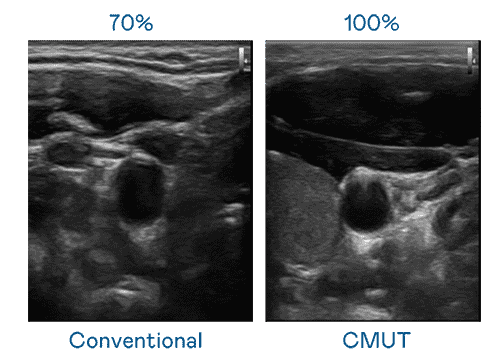

CMUT 技术是一种用电容式微机电元件来产生超音波讯号的技术。。与传统 PZT 压电式技术相比,,CMUT 频宽增加 30%,,更宽频的超音波讯号让影像解析度大幅提升,,,是实现高影像品质医疗超音波扫描、、、促进精准医疗发展的关键技术。。。。

大频宽带来超清晰影像

超音波影像的解析度高低,,首先取决于探头能发出的讯号频宽。。。MG电玩 CMUT 可提供高清晰的超音波讯号,,,提供高频宽、、、高灵敏度、、影像纹理细节更高的超音波影像,,,,协助医护人员缩短影像判读时间及利用精准的医疗影像进行诊断。。。。